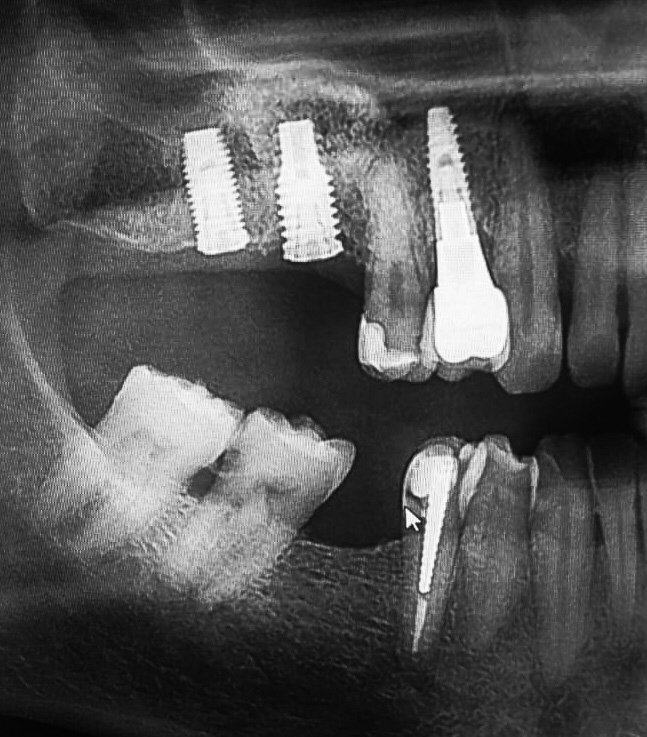

Hola compañeros, Acude a mi consulta un paciente al que le colocaron estos dos implantes hace 4 años. No se presentó a la cita para empezar las coronas por miedo [...]

Paciente masculino 38 , se cambio de pais busca rehabilitacion implante en 37 , creo que es un nobel pero no estoy seguro .

Paciente que acude con tornillos transoclusales rotos. Al parecer por segunda vez, lo que me lleva a pensar en un mal ajuste protético. Podriais ayudarme a identificar de que implantes [...]